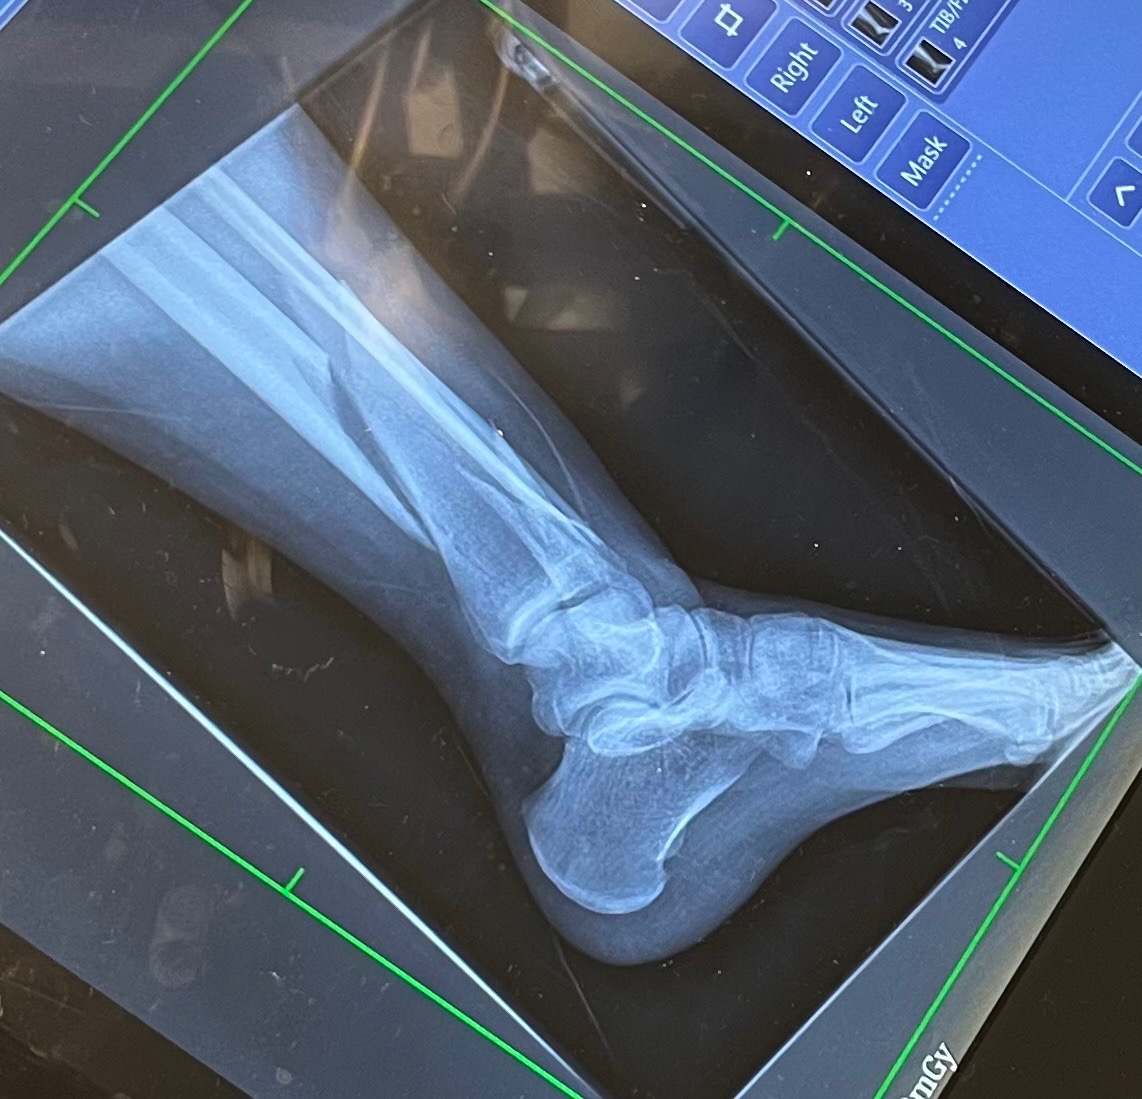

I was rushed to the ER. My partner en route, surrounded by strangers and in pain, I was out of my depth. After an X-ray and some morphine, I was told three things: that both bones in my left leg were broken, that my pain made sense, and that I would need to have surgery.

They sedated me, repositioned my floating bones, and put them in a temporary cast till my surgery. It hurt to move.